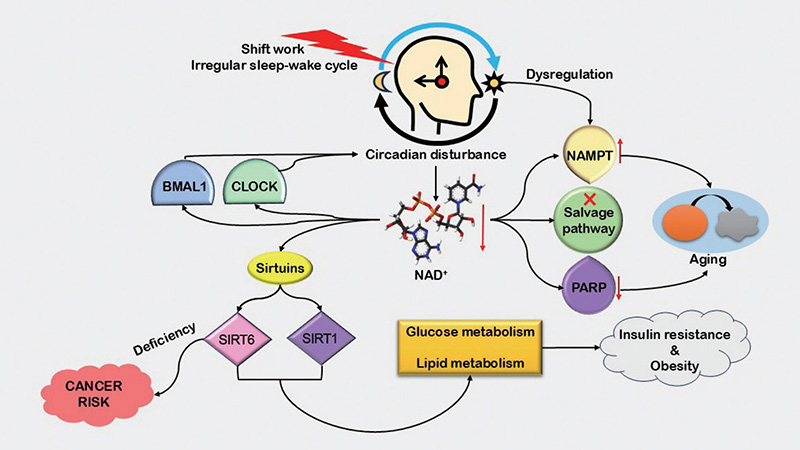

Cơ chế sinh học và nhịp sinh học

NAD⁺ nội sinh dao động theo nhịp sinh học (circadian rhythm). Việc bổ sung NMN liên tục trong 3 tháng giúp điều chỉnh nhịp NAD⁺–SIRT–CLOCK, duy trì hoạt động enzyme liên tục và tối ưu hóa các quá trình chuyển hóa năng lượng, sửa chữa DNA và tự thực bào.

Tác động của rối loạn nhịp sinh học đến chuyển hóa NAD⁺ và nguy cơ bệnh lý